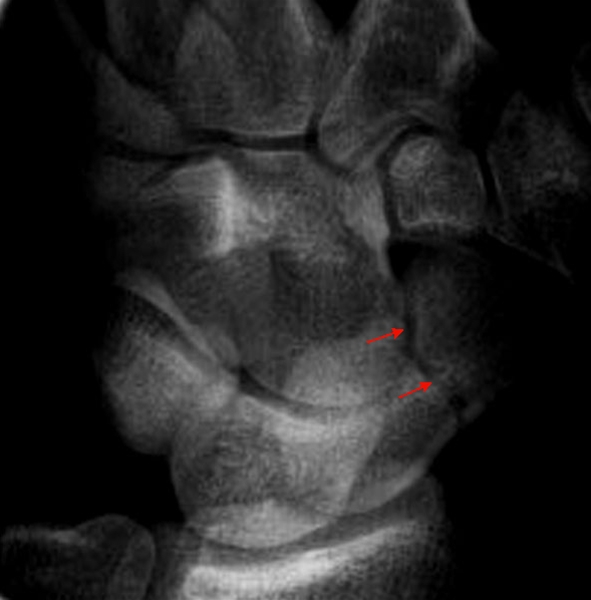

Schaphoidfraktur

Venstre håndrod. Tværfraktur gennem os scaphoideum (pil).

Frakturen kan være vanskelig at se akut, og medfører ofte langsom opheling eller pseudoartrose, hvis den ikke behandles. Almindelig røntgenbilleder suppleres derfor ofte med MR scanning for at stille diagnosen.